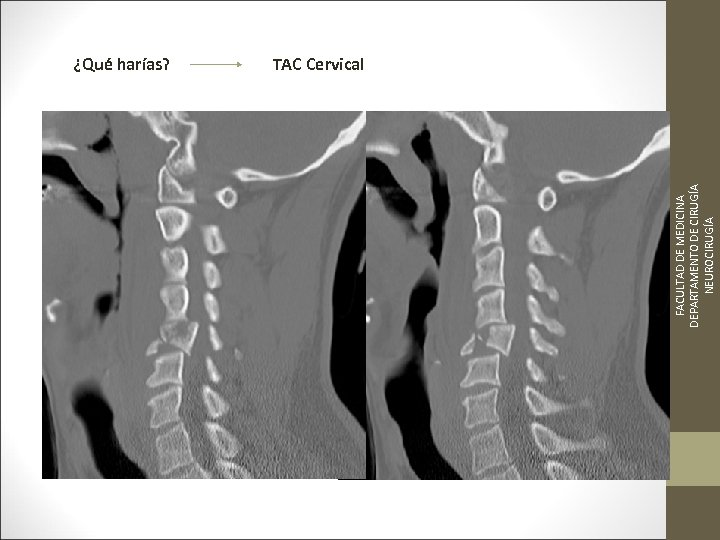

FACULTAD DE MEDICINA DEPARTAMENTO DE CIRUGÍA NEUROCIRUGÍA ¿Qué harías? TAC Cervical

TC Desplazamientos de fragmentos óseos ¿Algo mas? FACULTAD DE MEDICINA DEPARTAMENTO DE CIRUGÍA NEUROCIRUGÍA RM Desplazamientos discales y lesiones ligamentosa